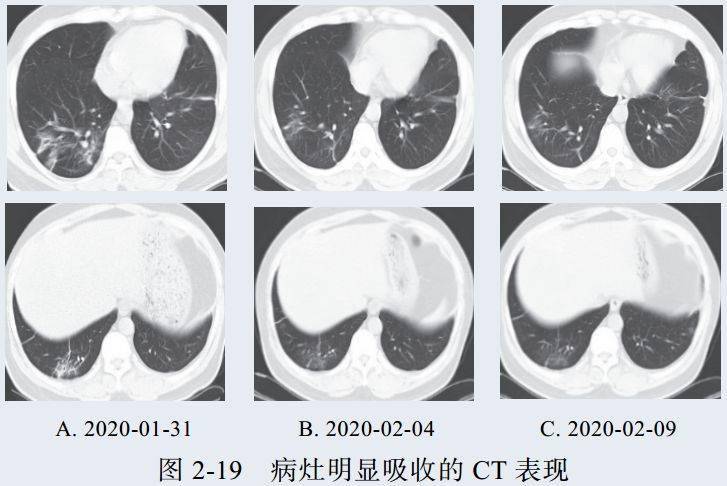

四、消散期征象

多数病例在 14 天后进入病灶消散期,表现为病灶逐步吸收,可遗留少许条索状高密度影,提示纤维化。少部分病例病程较短,影像可由早期表现直接进入消散期(图 2-17)